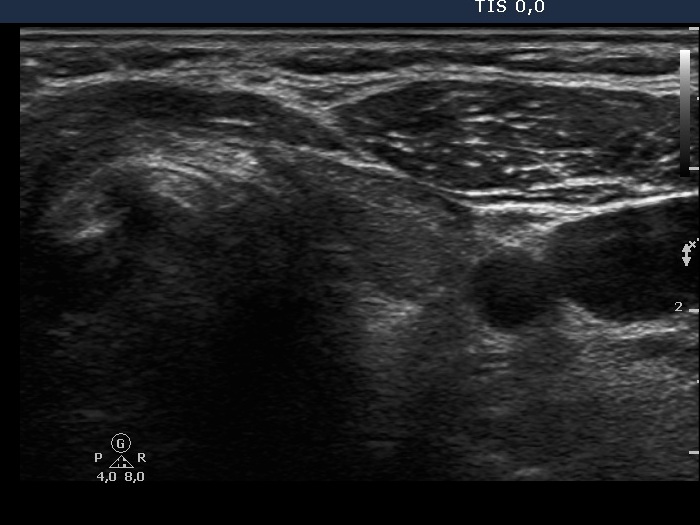

Clinical data: A 47-year-old woman underwent bilateral subtotal lobectomy for nodular goiter 6 years earlier. She was referred for regular follow-up examinations.

Ultrasonography. The thyroid was composed of circumscribed echonormal and minimally hypoechogenic areas divided by fibrous tissue. None of these areas corresponded to a nodule in a pathological sense.